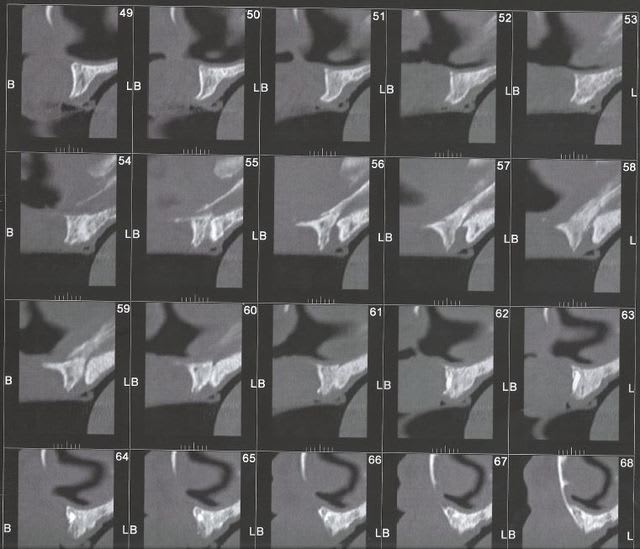

J'ai un patient qui souhaite faire une réhabilitation implantaire du maxillaire mais il refuse les sinus et les greffes.

Le problème, c'est qu'au vu du scan je pense pouvoir poser seulement trois implants (2 en secteur 1 et 1 en secteur).

Un quatrième secteur 2 juste avant la perte osseuse me semble très limite.

Je vous mets les scan en pj, si vous avez des idées (SANS GREFFE ni sinus au maximum ROG),je suis preneur.

Au niveau du secteur 2 , il y'avait un énorme kyste que j'ai prélevé et envoyé en biopsie (RAS) est-il possible d'imaginer une ROG avec les seules paroi osseuses latérales ???

maintenant ca a l'air pas si mal sur ton scan il faut mesurer, mais des 3X10 ca doit passer

Vers la coupe 82-83, y'aurait pas un petit espace exploitable ?